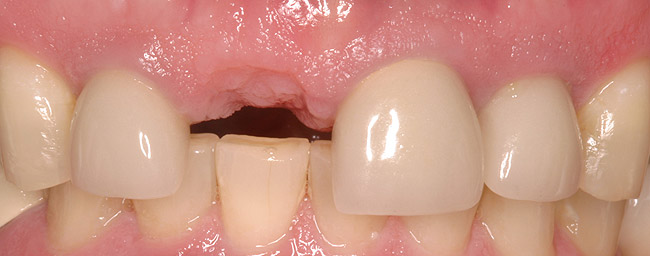

Figure 6a  Upper right central incisor, history of trauma, existing RCT and restoration unsatisfactory.

Figure 6a

Figure 6b  Upper right central incisor, history of trauma, existing RCT and restoration unsatisfactory.

Figure 6b

Figure 6c  Upper right central incisor, history of trauma, existing RCT and restoration unsatisfactory.

Figure 6c